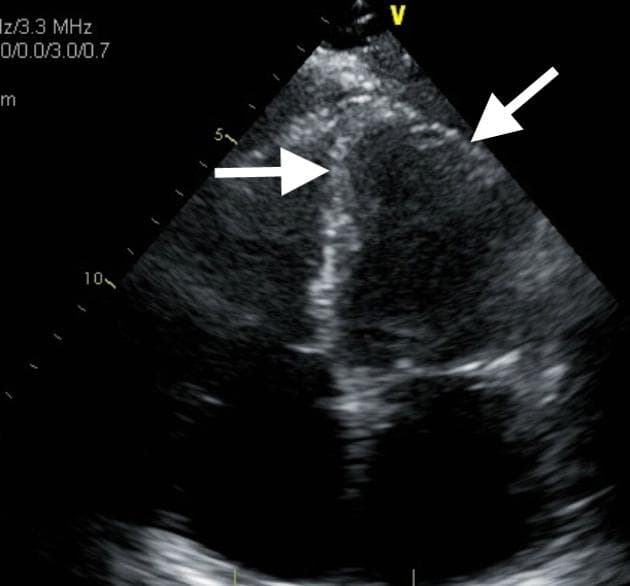

Đau ngực, men tim troponin T tăng: 1,4 µg/L, CK 19,2 µmol/L, LDH 6,3 µmol/L và C-reactive protein (CRP): 17 mg/L. Chức năng tim giảm nhẹ trên siêu âm tim. Bệnh lý động mạch vành và các dị dạng được loại trừ bằng CTA.

- Tràn dịch màng phổi (pleural effusion) hai bên nhỏ.

- Tăng quang nhẹ màng ngoài tim không kèm dày thành, liền kề thành tự do thất trái.

Hình ảnh cộng hưởng từ tim (Cardiac MRI) phù hợp với thay đổi viêm cấp tính toàn bộ thành bên cơ tim hoặc viêm cơ tim cấp tính (acute myocarditis).

Trường hợp này là ví dụ về đặc trưng mô cơ tim trên bệnh nhân có các dấu hiệu điển hình của viêm cơ tim.

Theo tiêu chuẩn Lake Louise, cả hai tiêu chuẩn chính đều được đáp ứng 2:

- Phù cơ tim (myocardial edema) (dựa trên hình ảnh T2W hoặc bản đồ T2)

- Tổn thương cơ tim không do thiếu máu (non-ischemic myocardial injury) (T1 tự nhiên bất thường, ECV bất thường hoặc tăng quang muộn - LGE)

Ngoài ra, có rối loạn chức năng tâm thu nhẹ, điều này củng cố thêm chẩn đoán và đáp ứng một trong các tiêu chuẩn hỗ trợ (viêm màng ngoài tim, rối loạn chức năng tâm thu).